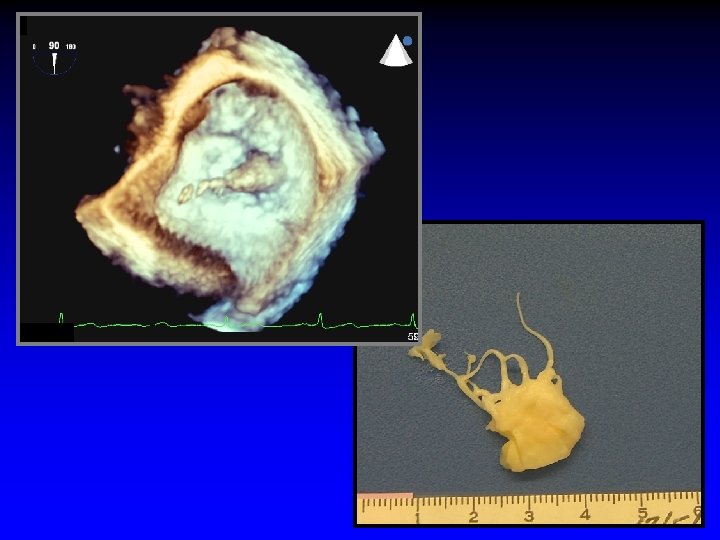

Case 3 Ruptured cords A 2 and A 3

Surgeon’s roadmap A 2 and A 3